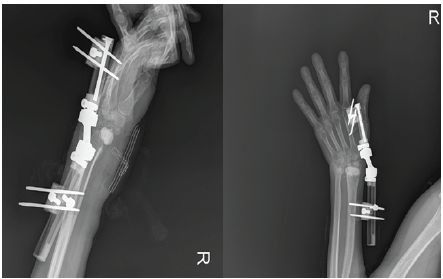

An external fixator was applied to achieve wrist distraction, and an antibiotic-impregnated spacer was prepared and placed within the joint (Figure 2).

Figure 2: The first stage of the two-stage surgical approach involved placement of an antibiotic-impregnated spacer and a monolateral external fixator.